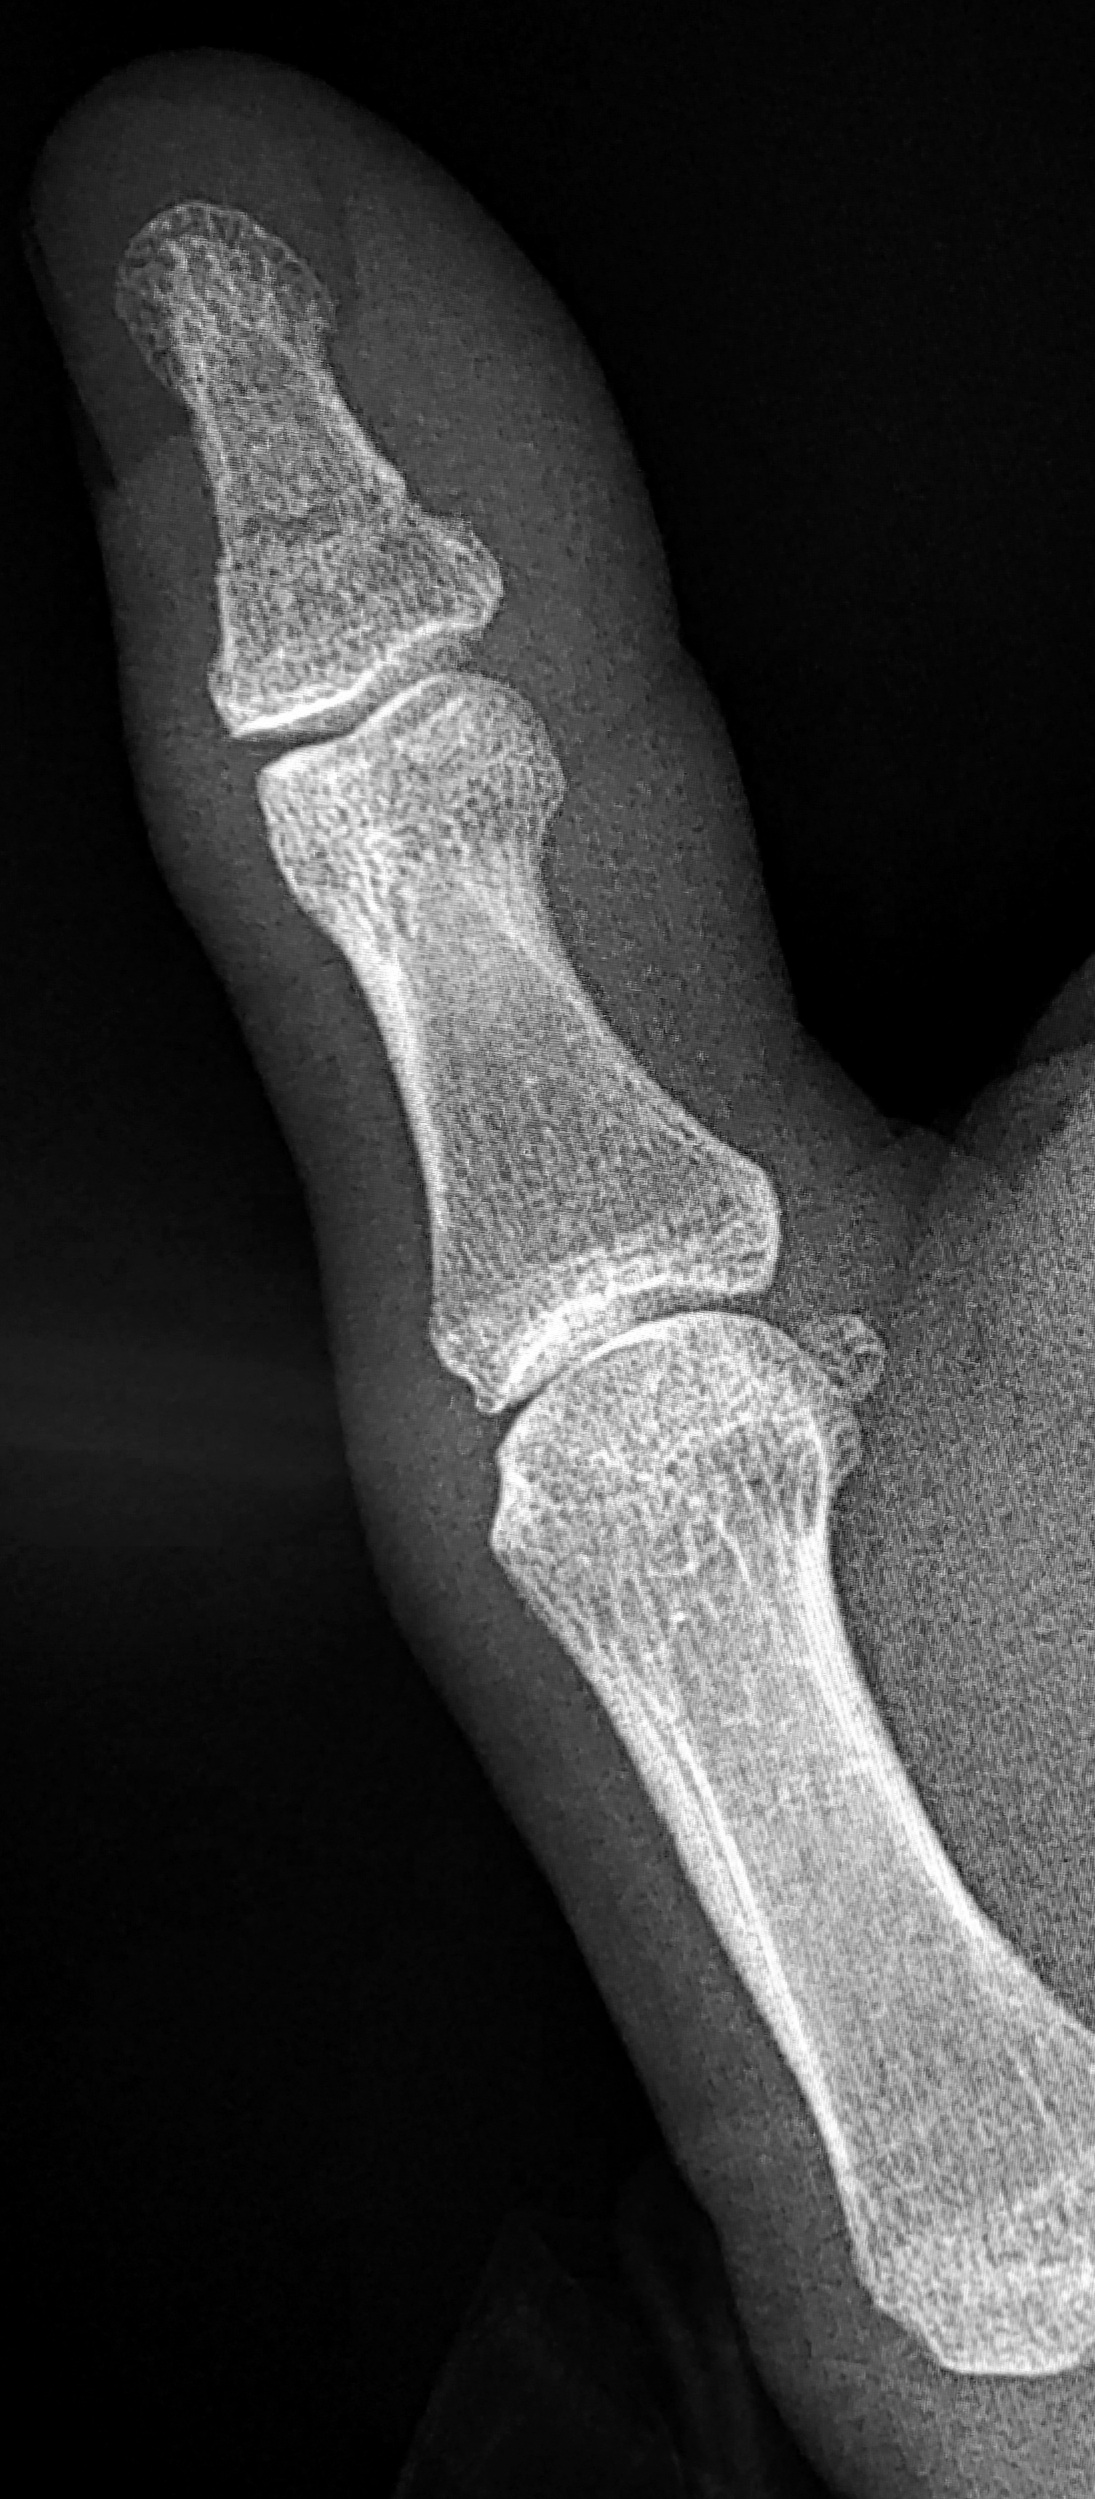

Thumb Delta Phalanx . The delta phalanx can be triangular, trapezoidal or almost round in shape. Angular deformity of the thumb is most often caused by a delta phalanx or a longitudinally bracheted diaphysis in a triphalangeal thumb. The thumb is often included in the syndactyly, or it may carry a delta phalanx with radial inclination. Delta phalanx (longitudinally bracketed epiphysis) congenital triangular bones in the hand. Clinodactyly is a congenital condition of the hand, often associated with down's syndrome, that is characterized by the abnormal curvature of a digit in the radioulnar plane. Delta phalanx, or type iii clinodactyly, can be diagnosed by observing a patient with a triangular or trapezoidal shaped bone, usually in the thumb or. Triphalangeal thumb is a rare congenital anomaly in which the thumb has three phalanges. The delta phalanx, also known as a longitudinal epiphyseal bracket or clinodactyly with delta phalanx, is an uncommon deformity of the proximal phalanges and metacarpals. Delta formation occurs in tubular bones with a proximal epiphysis like the.

Delta formation occurs in tubular bones with a proximal epiphysis like the. Delta phalanx (longitudinally bracketed epiphysis) congenital triangular bones in the hand. The delta phalanx can be triangular, trapezoidal or almost round in shape. The delta phalanx, also known as a longitudinal epiphyseal bracket or clinodactyly with delta phalanx, is an uncommon deformity of the proximal phalanges and metacarpals. Triphalangeal thumb is a rare congenital anomaly in which the thumb has three phalanges. Clinodactyly is a congenital condition of the hand, often associated with down's syndrome, that is characterized by the abnormal curvature of a digit in the radioulnar plane. The thumb is often included in the syndactyly, or it may carry a delta phalanx with radial inclination. Angular deformity of the thumb is most often caused by a delta phalanx or a longitudinally bracheted diaphysis in a triphalangeal thumb. Delta phalanx, or type iii clinodactyly, can be diagnosed by observing a patient with a triangular or trapezoidal shaped bone, usually in the thumb or.

Thumb Delta Phalanx Angular deformity of the thumb is most often caused by a delta phalanx or a longitudinally bracheted diaphysis in a triphalangeal thumb. Clinodactyly is a congenital condition of the hand, often associated with down's syndrome, that is characterized by the abnormal curvature of a digit in the radioulnar plane. Delta phalanx (longitudinally bracketed epiphysis) congenital triangular bones in the hand. Delta phalanx, or type iii clinodactyly, can be diagnosed by observing a patient with a triangular or trapezoidal shaped bone, usually in the thumb or. The delta phalanx can be triangular, trapezoidal or almost round in shape. Angular deformity of the thumb is most often caused by a delta phalanx or a longitudinally bracheted diaphysis in a triphalangeal thumb. The thumb is often included in the syndactyly, or it may carry a delta phalanx with radial inclination. Delta formation occurs in tubular bones with a proximal epiphysis like the. The delta phalanx, also known as a longitudinal epiphyseal bracket or clinodactyly with delta phalanx, is an uncommon deformity of the proximal phalanges and metacarpals. Triphalangeal thumb is a rare congenital anomaly in which the thumb has three phalanges.